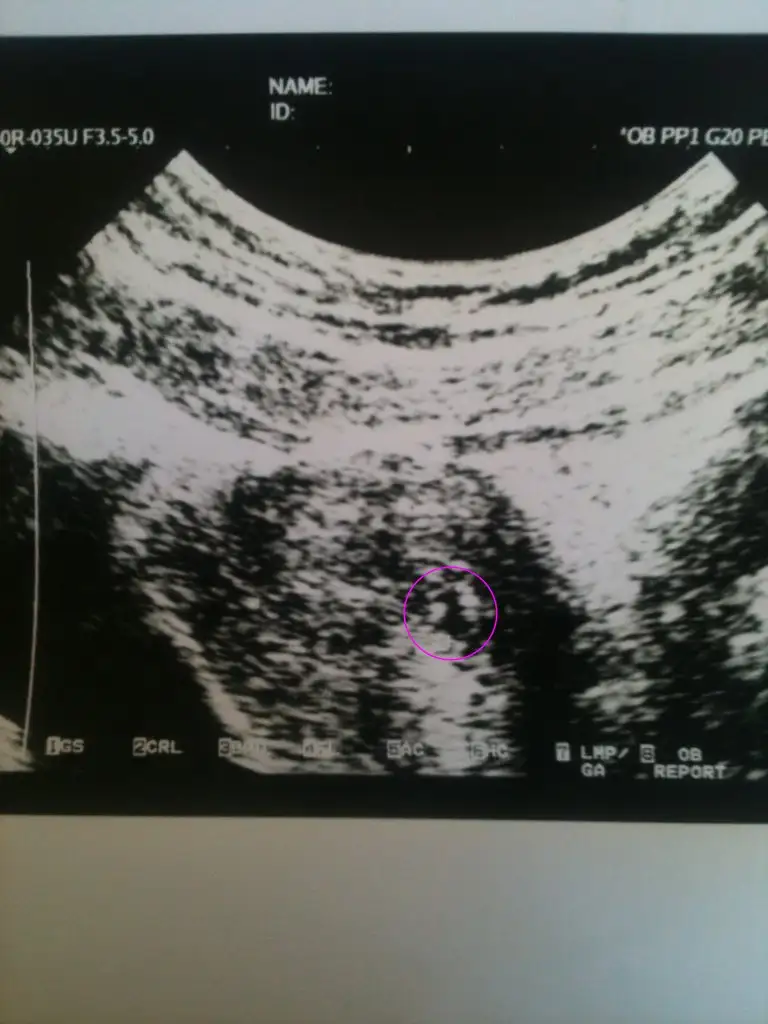

4 hafta + 3 günlük hamilesin. Yani 5. haftanın 3. günündesin :) 2 gün sonra tahminen kesen gözükür. Çokta ihmal etmeyin, bu topicte bir arkadaşımıza doktor 5 günlük yatak izni verdi. Usg de hafif kanama görmüş